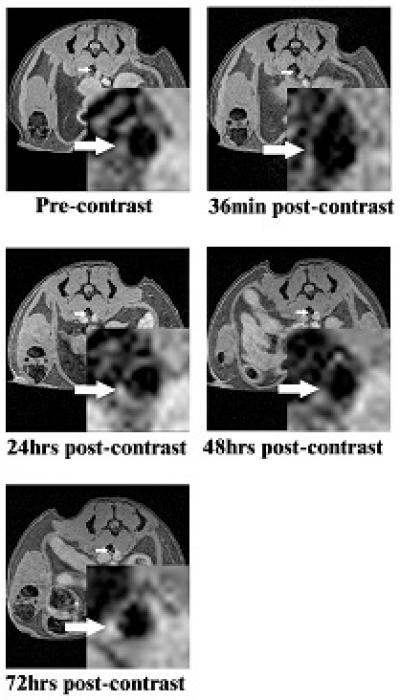

Twenty-four hours after injecting the HDL-like molecules into mice, MRI tests showed that measuring and assessing cholesterol-filled cells in the arterial walls yielded a 79 percent increase in detection compared with the initial baseline images taken the day before. Mice without the plaques showed no enhancement of imaging.

The effects of the contrast agent provided a viewing window of up to 48 hours. In addition, the strength of the signal correlated with the presence of the macrophage cells in which cholesterol accumulated. The more cholesterol-filled cells in an area, the brighter the signal.